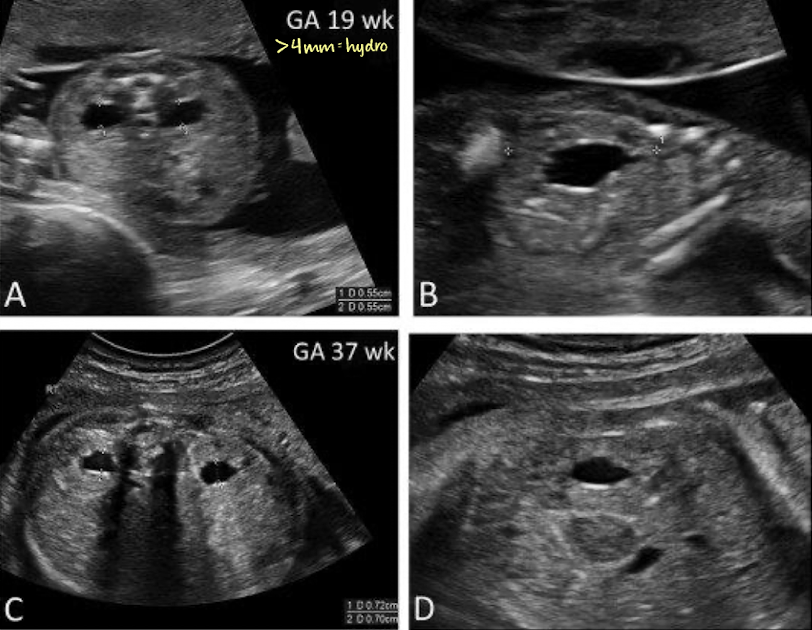

mild pyelectasis (dilation) vs. hydronephrosis in utero

before 27w = >4mm is abnormal

after 27w = >7mm is abnormal

renal pelvis measurement for hydro

>4mm = hydro